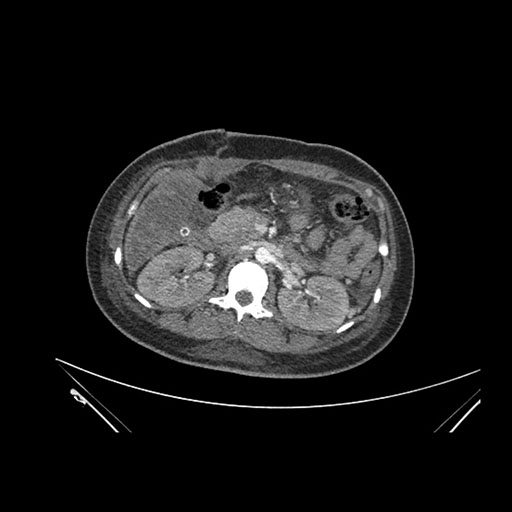

Imaging Analysis

Look through the patient's CT scan to identify any areas of concern for the necessary procedure.

Axial Arterial

Based on initial findings, which issue(s) would you be most concerned about?